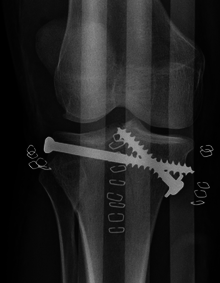

![]() A severe tibial plateau fracture | |

Treatment is aimed at achieving a stable, aligned, mobile and painless joint and to minimize the risk of post-traumatic osteoarthritis. To achieve this operative or non-operative treatment plans are considered by physicians based on criteria such as patient characteristics, severity, risk of complications, fracture depression and displacement, degree of injury to ligaments and menisci, vascular and neurological compromise. For early management, traction should be performed early in ward. It can either be Skin Traction or Skeletal Traction. Depends on the body weight of patient and stability of the joint. Schantz pin insertion over the Calcaneum should be done from Medial to lateral side. Later when condition is stable. Definitive plan would be Buttress Plating and Lag Screw fixation.